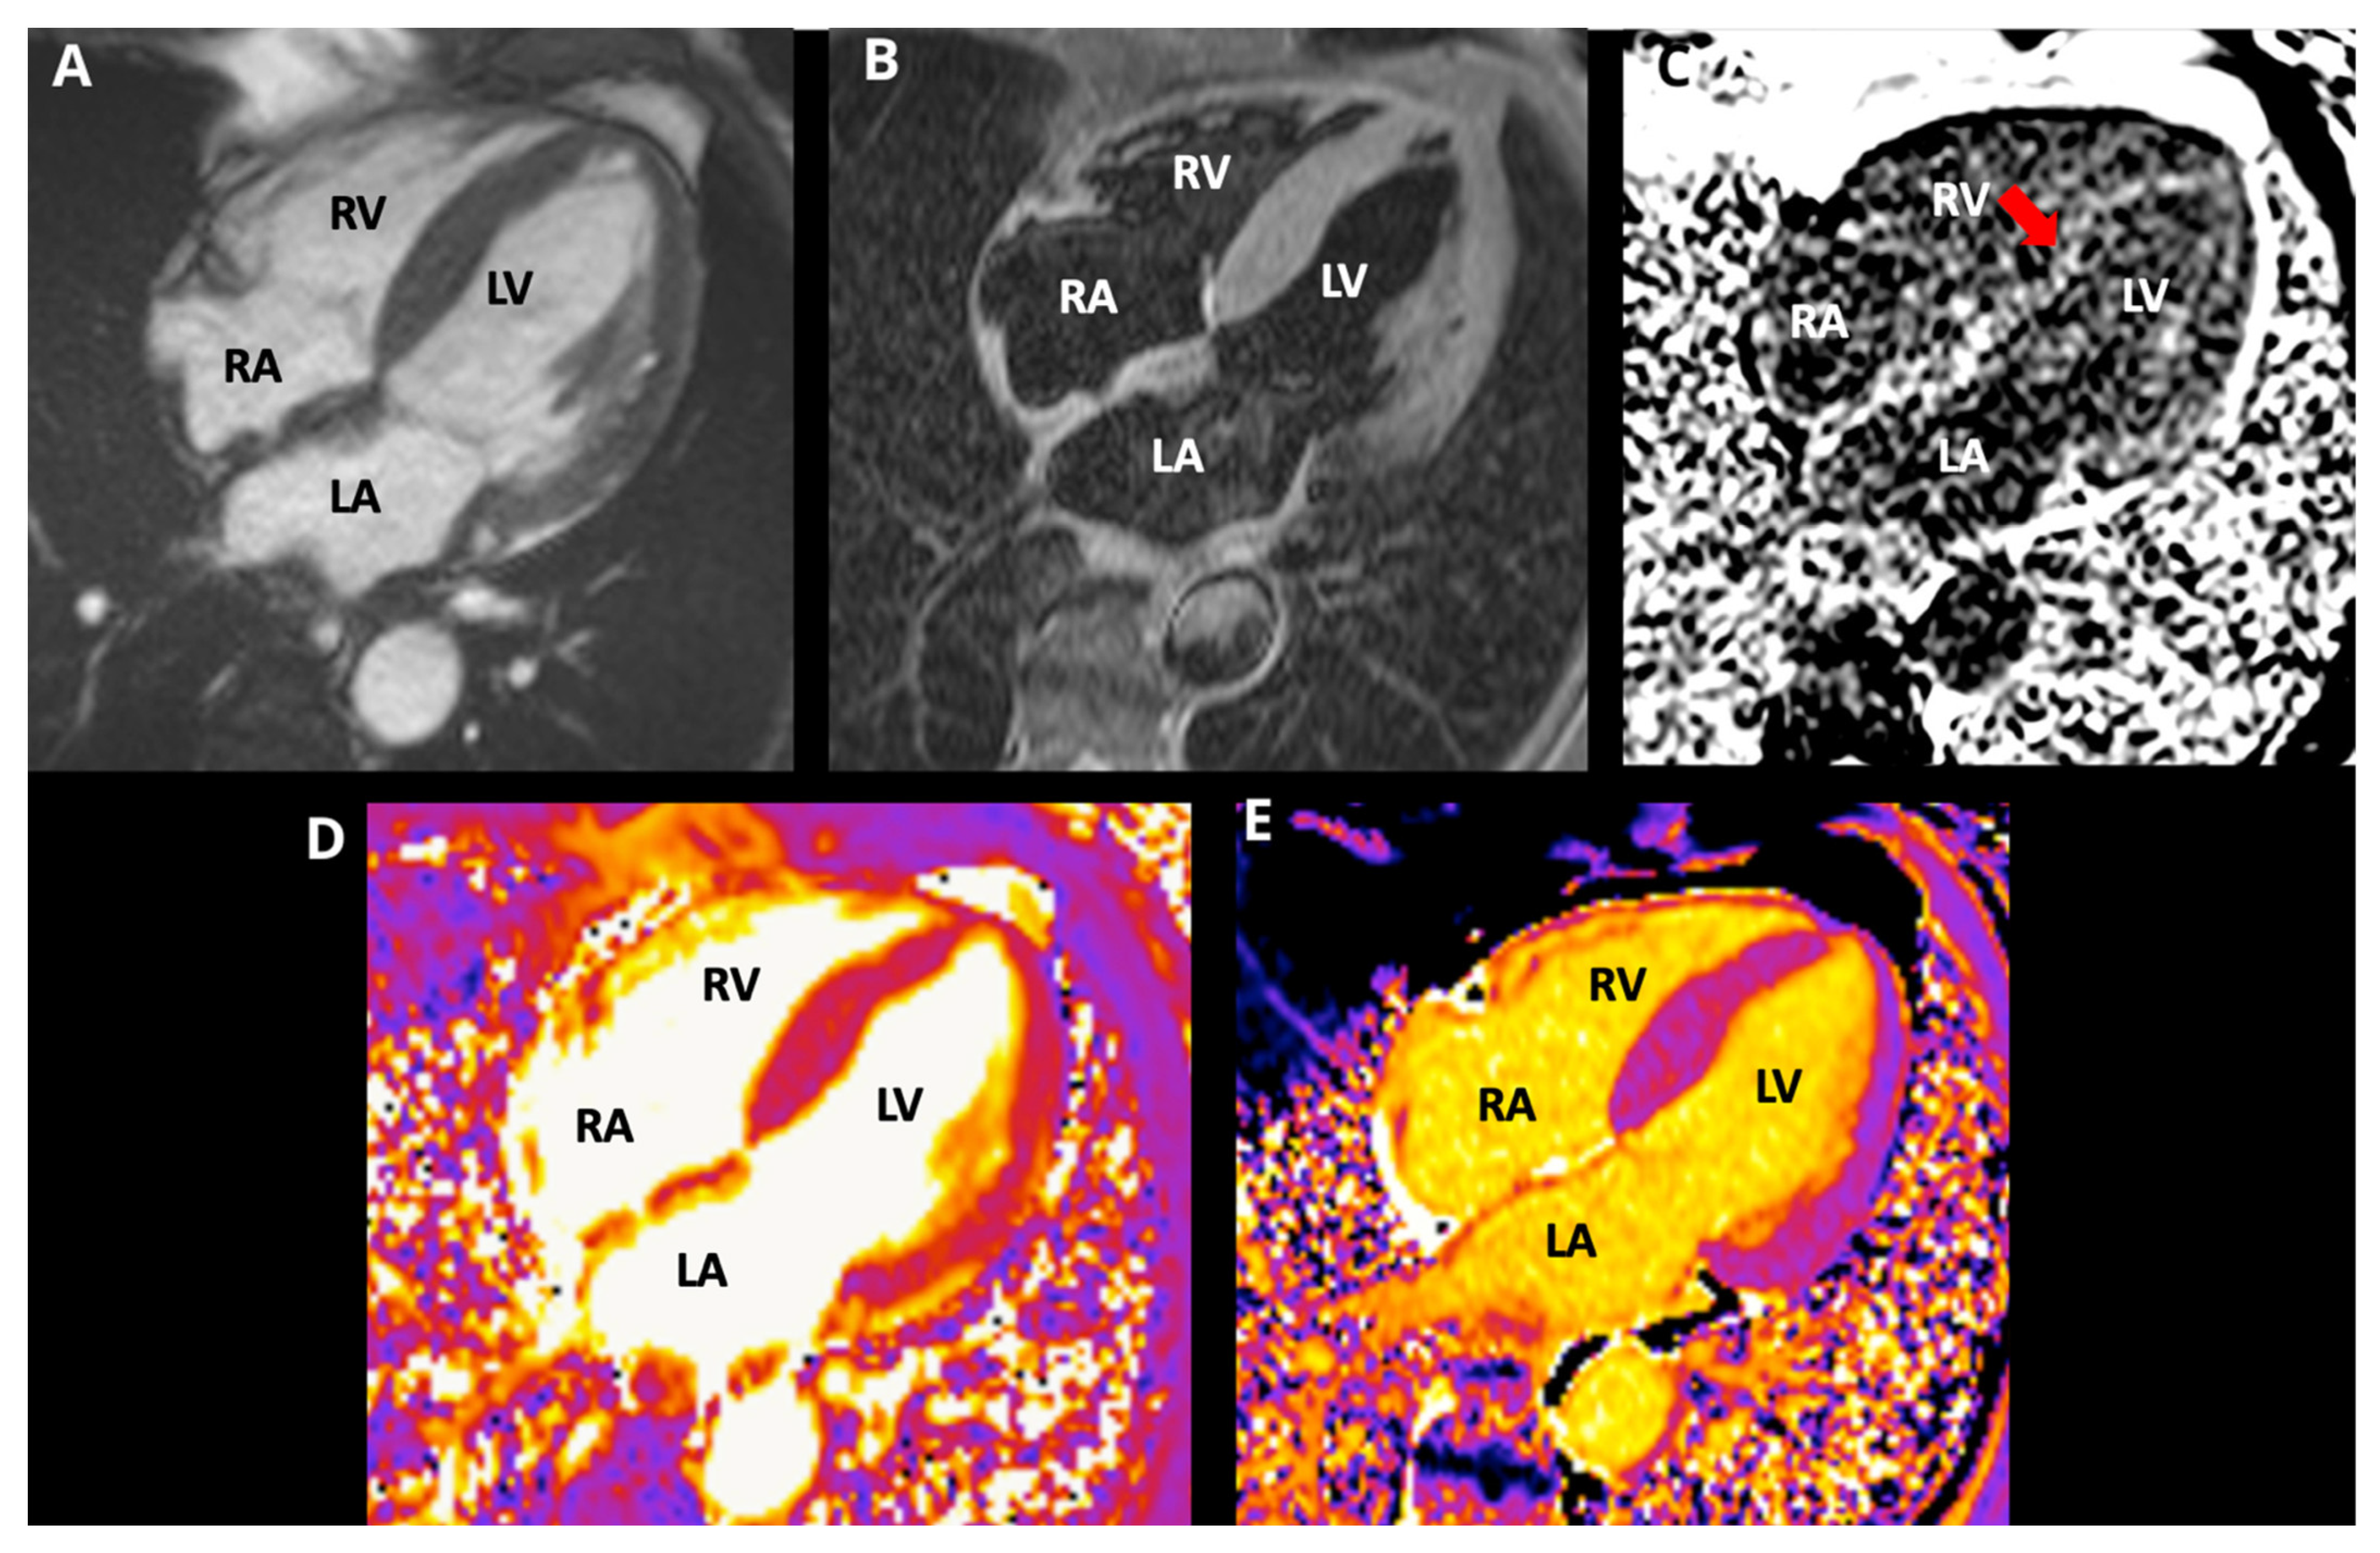

| Cardiac Magnetic Resonance (CMR) | Tissue characterization: diffuse subendocardial LGE; quantitative mapping (↑ native T1, ↑ ECV) improves sensitivity; atrial/septal involvement | Patterns overlap among amyloid types; gadolinium limited in renal dysfunction; requires expertise/availability | Strongly supports amyloidosis but does not definitively type ATTR vs. AL |